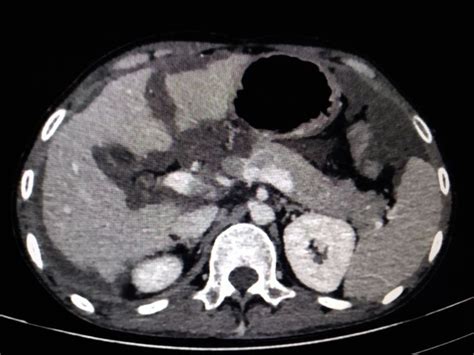

When it comes to diagnosis, doctors usually start with a thorough medical history and physical examination. If PMP is suspected, imaging studies are crucial. CT scans (Computed Tomography) and MRIs (Magnetic Resonance Imaging) are the go-to tools. These scans allow doctors to visualize the abdominal cavity, identify the presence of mucin, and assess its extent and distribution. They can also help pinpoint the potential primary source, like an appendiceal tumor. However, imaging alone may not always provide a definitive diagnosis. Blood tests might be performed, but there aren’t specific markers for PMP. The definitive diagnosis of PMP is typically made through biopsy . This can be done during surgery, where tissue samples of the mucin and affected tissues are taken and examined under a microscope by a pathologist. The pathologist looks for specific cellular characteristics that confirm the presence of mucinous tumor cells and the characteristic gelatinous material. Sometimes, a diagnostic laparoscopy might be performed, which involves inserting a small camera into the abdomen to get a closer look and take biopsies. The challenge in diagnosing PMP lies in its insidious onset and the nonspecific nature of its early symptoms. Patients often present with symptoms that mimic other common gastrointestinal issues, leading to a delay in seeking specialized medical attention. The key takeaway here is that if you notice persistent, unexplained changes in your abdomen, it’s always worth getting it checked out by a healthcare professional. Early detection, even with a slow-growing condition like PMP, can significantly improve outcomes.